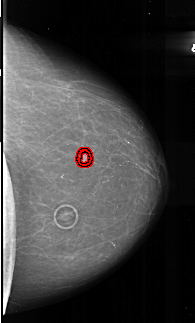

A_1010_1.RIGHT_CC

RIGHT_CC LINES 5491 PIXELS_PER_LINE 3301 BITS_PER_PIXEL 16 RESOLUTION 42 OVERLAY

FILE: A_1010_1.RIGHT_CC.OVERLAY

TOTAL_ABNORMALITIES 1

ABNORMALITY 1

LESION_TYPE MASS SHAPE IRREGULAR MARGINS SPICULATED

ASSESSMENT 5

SUBTLETY 4

PATHOLOGY MALIGNANT

TOTAL_OUTLINES 2

BOUNDARY

CORE